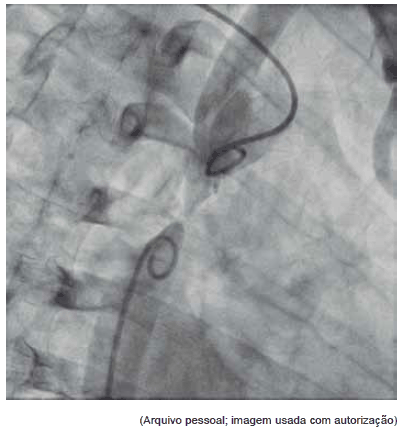

Esta angiografia diz respeito a:

Provas